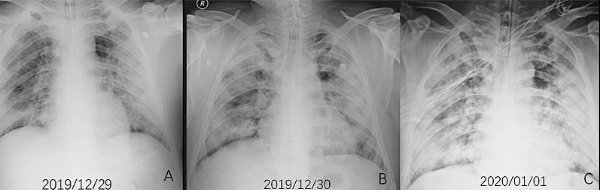

Koronavirüs belirti ve şiddetinin her hastada farklılık gösterdiğine dikkat çeken uzmanlar, hastalık sürecinin ağır geçirilmesinin nedenini, görevi vücutta virüsün çoğalmasını durdurmak olan Tip 1 İnterferon proteninin bulunmaması olarak gösteriyor.

Vücuttaki görevi virüsün çoğalmasını durdurmak olan Tip 1 İnterferon, enfeksiyonu tespit ettiği anda bağışıklık sistemi tarafından üretiliyor.

Hastalarda koronavirüsün ağır geçirilmesinin nedeni de Tip 1 İnterferon sinyal ağının bozulmasından kaynaklanıyor. Kovid- 19 Genetik Yatkınlık Testi ile bunu tespit edebiliyoruz" dedi.